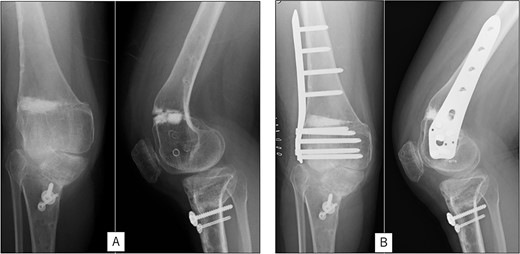

A 23-year-old woman presented with bilateral knee pain and gait abnormalities owing to marked lower extremity deformity. She was diagnosed with EVC as a child but had never been followed up by orthopedics because she was not in pain. On physical examination, marked valgus instability was observed in both knees, and the motion of both knees ranged from 10° to 135°. Radiographic examinations of both knees, including computed tomography, showed valgus deformity, lateral and anterior depression of the proximal lateral tibial plateau, and external rotation deformity of the lower leg. Patellar dislocation was observed in the right knee (Fig. 1). The radiological angles are presented in Table 1. The right knee underwent surgery first, followed by the left 10 months later. Lateral and medial skin incisions were made. Extensive lateral retinacular release, fractional lengthening of the distal lateral hamstring, and Z-lengthening of the iliotibial band were then performed. At this stage, peroneal nerve strain was identified, and decompression of the peroneal nerve was performed. Osteotomy was subsequently performed on the tibia. Closed-wedge varus and derotational osteotomy of the proximal tibia and open-wedge varus osteotomy of the distal femoral varus were performed. In addition, vastus medialis advancement was performed on the right knee, and patellar realignment was achieved in extension (Fig. 2). However, the knee showed a subluxation tendency owing to flexion of >30°; therefore, the postoperative rehabilitation plan progressed more slowly than that of the left knee. Range of motion training began on the left knee immediately after surgery without any restrictions, but on the right knee only after 3 weeks of postoperative immobilization in the extended position. However, ambulation exercise was performed on both knees with no loading for 3 weeks, then partial loading was initiated, and full loading was permitted at 8 weeks postoperatively. Early postoperative standing radiography showed residual mild valgus deformity of the lower limbs (Fig. 2, Table 2). In addition, the right knee showed patellar re-dislocation 2 months postoperatively, and the patellar deformity gradually progressed owing to the femoral implant; therefore, the patient underwent implant removal, tibial tubercle transfer, and medial patellofemoral ligament reconstruction 1.5 years after the initial surgery (Fig. 3). Six months later, she fell while walking and developed a fracture at the osteotomy of the right femur; open reduction and internal fixation were performed (Fig. 4). The remaining years passed uneventfully, and 10 years after the initial surgery, the patient still had mild valgus deformity of the lower limbs, but had no recurrence other than that experienced immediately after surgery, no complaints of knee pain, and a stable gait (Fig. 5, Table 2).

Preoperative radiography and computed tomography: (A) anteroposterior and lateral views of the right knee, (B) skyline view of the right knee, (C) anteroposterior and lateral views of the left knee, (D) skyline view of the left knee, (E) standing anteroposterior view, and (F) 3D image of the entire lower limb.